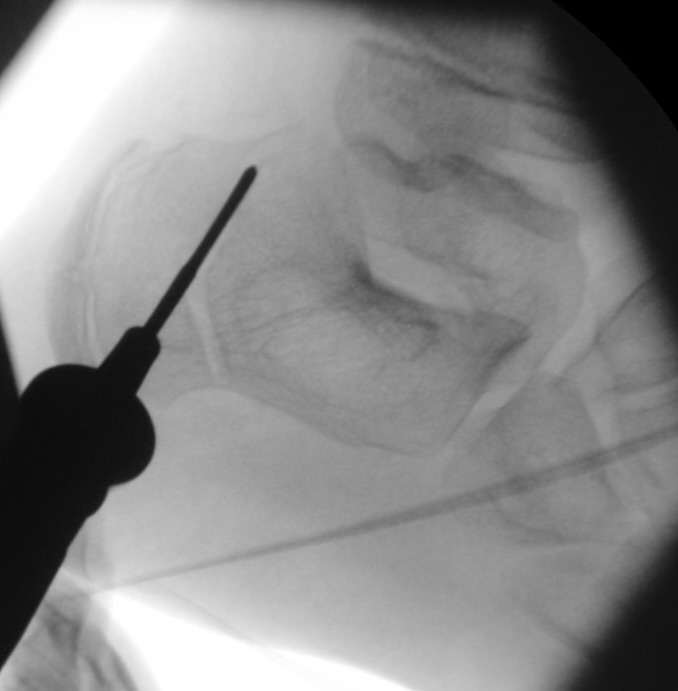

In der minimalinvasiven Fußchirurgie ist es unabdingbar, die Fräse in ihrer Position zum Knochen radiologisch zu kontrollieren, damit vulnerable Wachstumsfugen oder angrenzende Gelenke nicht verletzt werden. Zu diesem Zweck werden mit einem Bildwandler während der Operation die genaue Position der Fräse und der Osteotomieverlauf überprüft, was die Strahlenbelastung im Vergleich zu offenen Verfahren erhöht. Diese Strahlenbelastung hat potenziell einen schädigenden Einfluss auf den noch blutbildenden Knochen von Heranwachsenden. Gesicherte Landmarken am Fuß können die notwendige Zahl der Röntgenbilder und damit die Strahlung minimieren. Ist es erforderlich, mehrere Knochen zu osteotomieren, wie zum Beispiel im Bereich der Kleinzehen, werden anhand der Landmarken kleine Injektionsnadeln auf Höhe der geplanten Osteotomien vorgelegt und radiologisch im Bildwandler (BV) dokumentiert (Abb. 11). Ein solches Bild schafft eine gute Orientierung, sodass auf radiologische Kontrollen intraoperativ weitestgehend verzichtet werden kann.

Abb. 11: Lokalisation mehrerer Stichinzisionen mit einem Röntgenbild.